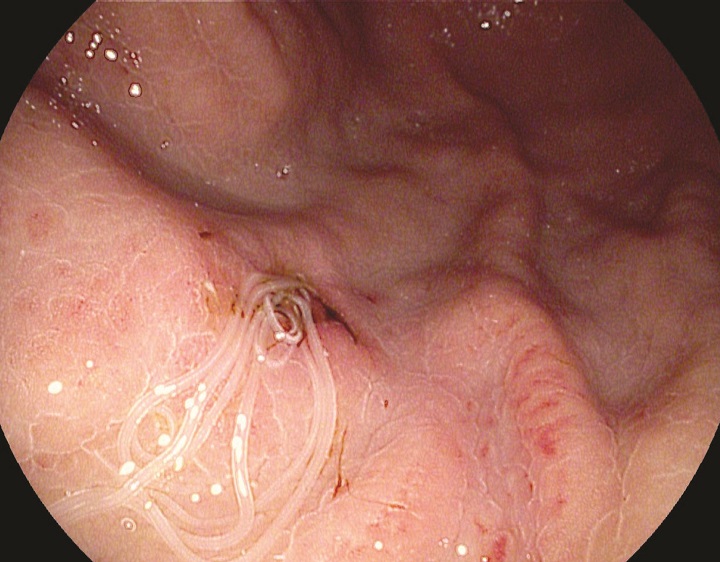

Canadian man hospitalized after eating worms in homemade salmon sushiHe made sushi at home using raw salmon he bought at a grocery store and within an hour he was in the emergency room, according to a new Canadian study.HealthJan 21, 2016

![]()